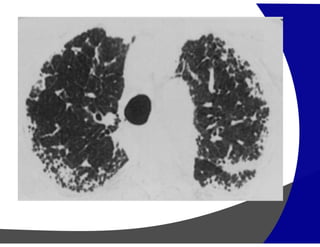

Consolidação

Preenchimento do espaço áereo apagando as estruturas

vasculares

Causas

• Edema: insuficiência cardíaca, SARA

• Hemorragia: trauma

• Pus: infecção (pneumonia)

• Células: tumores

• Lipoproteína: proteinose alveolar

(Pneumonia Intersticial Aguda)